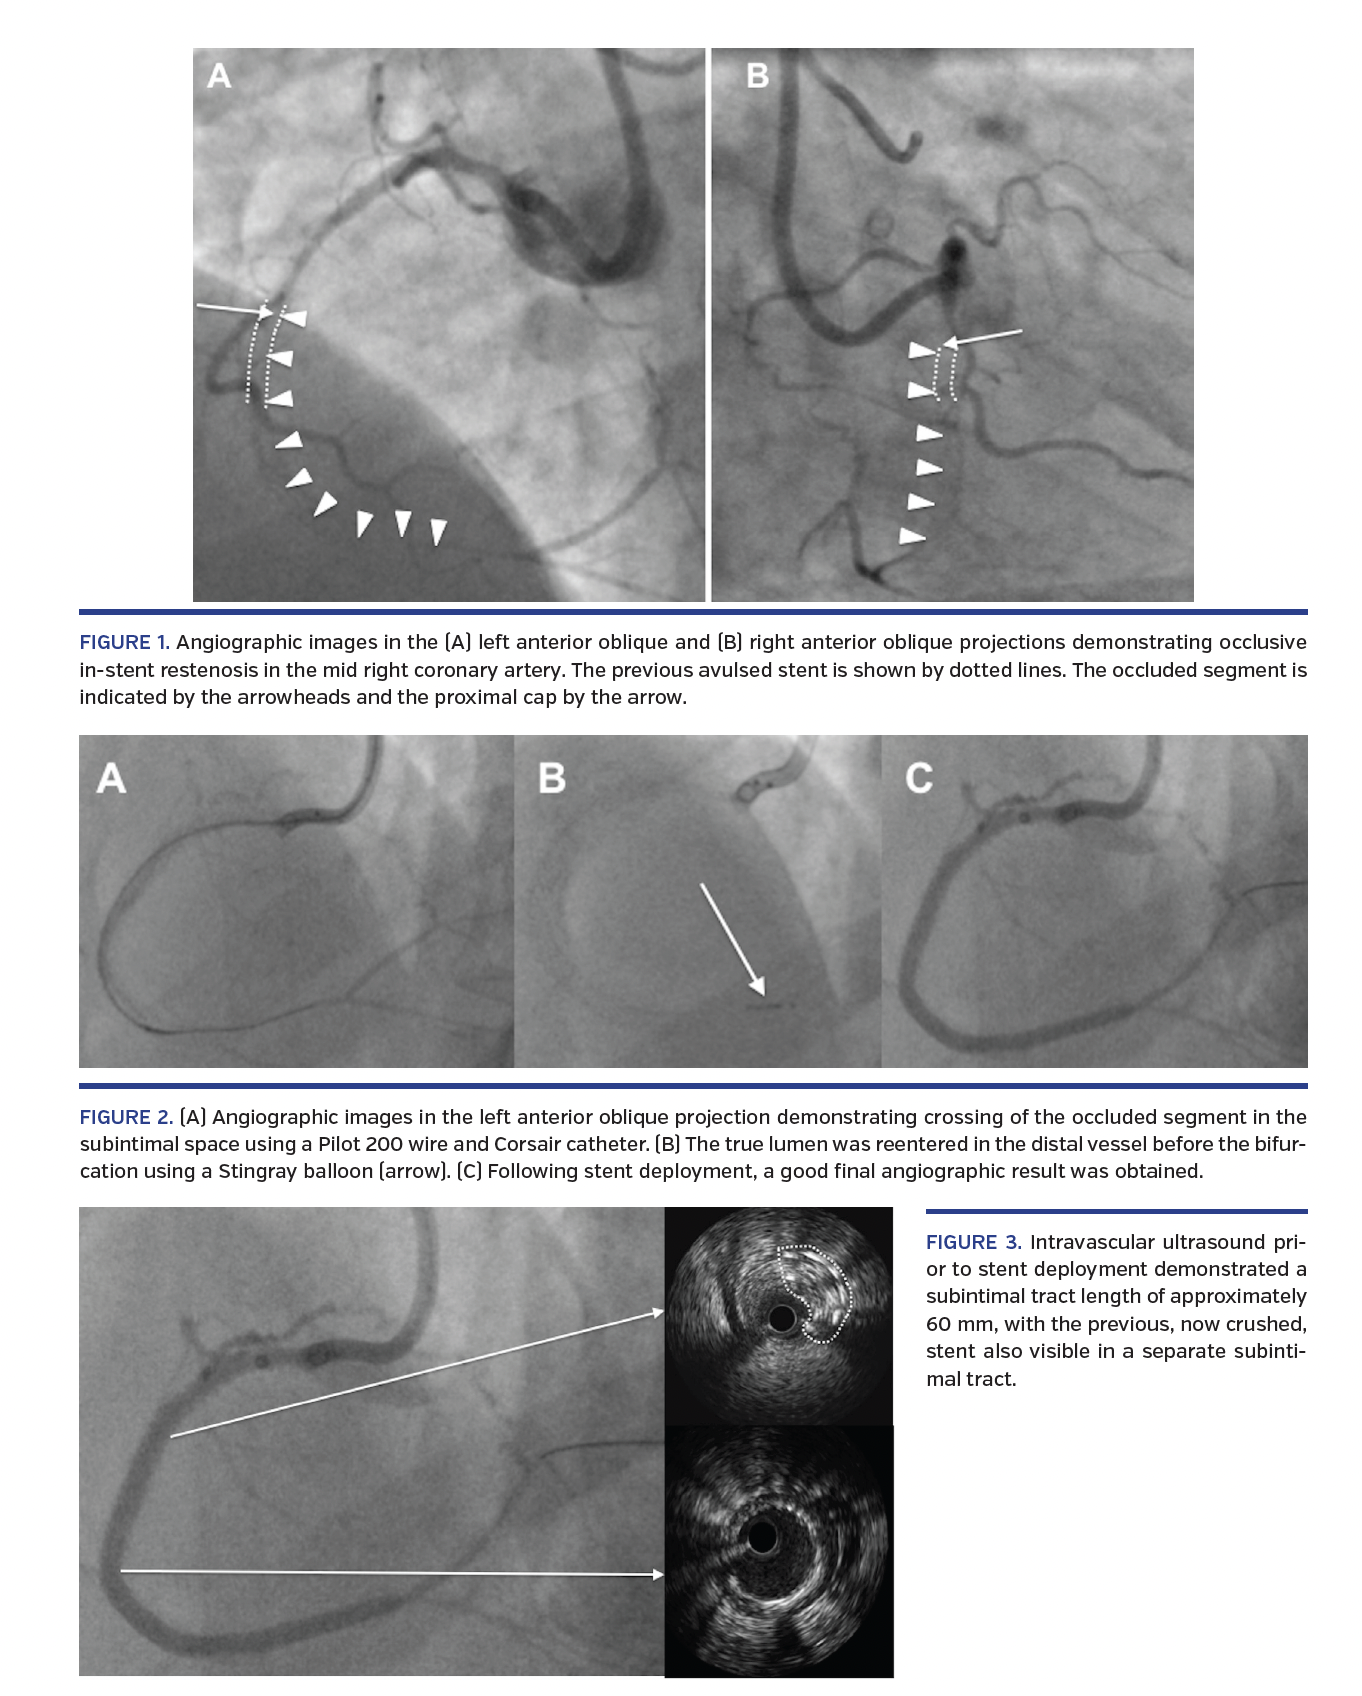

A 60-year-old male presented with Canadian Cardiovascular Society class III/IV angina progressive over several years despite maximal medical therapy. He had previously undergone percutaneous coronary intervention (PCI) to a dominant right coronary artery (RCA). Coronary angiography demonstrated occlusion of the RCA with the proximal cap of the occlusion located proximal to the previous stent (Figure 1).

Eventually using an anchor balloon inflated in the proximal vessel, a highly penetrative wire (15 g, ProVia; Medtronic) was advanced into the subintimal space outside the previous stent. The occluded segment was then traversed in the subintimal space using a Pilot 200 polymer wire (Abbott Vascular) and a Corsair catheter (Asahi Intecc) (Figure 2A). The true lumen was reentered in the distal vessel before the bifurcation using a Stingray balloon (Boston Scientific) and guidewire (Figure 2B). Two overlapping drug-eluting stents (Promus 2.5 x 38 mm and 3.0 x 38 mm; Boston Scientific) were subsequently deployed with a good final angiographic result (Figure 2C). Intravascular ultrasound demonstrated a subintimal tract length of approximately 60 mm; good apposition of the newly implanted stents with the previous (now crushed) stent was also visible (Figure 3).